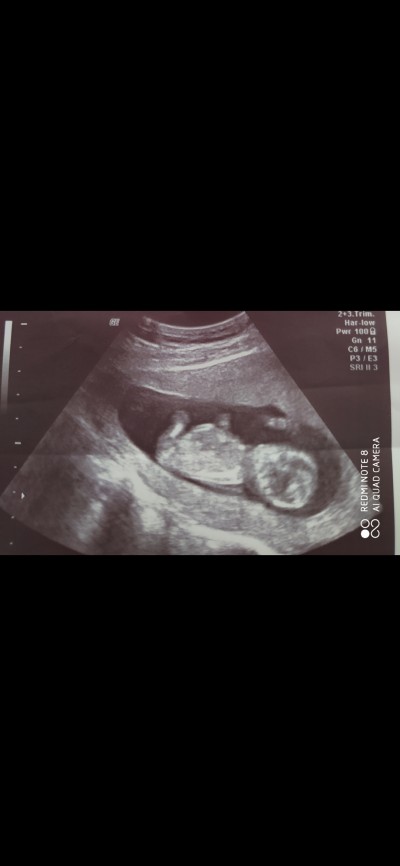

Bugün doktora gittim 13hafdadayım ve gayet iyi dedi şükür ama cinsiyet tahmin etdi  yinede  fotorafini paylaşdım tahmin ederseniz sevinirim

Gebelik haftası 13

Erkek gibi sanki

Bende yapısını erkeğe benzetim

%50 erkek %50 kiz